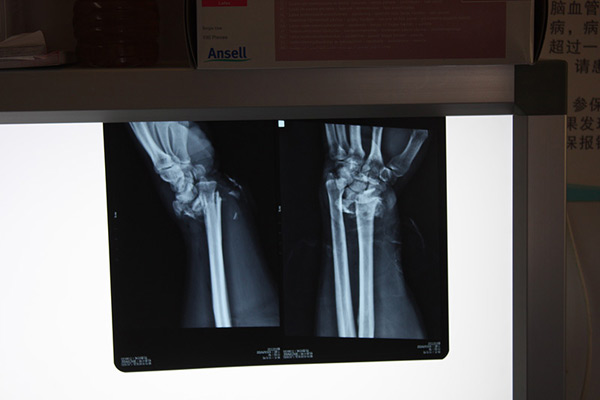

麻醉科主任李蕾考虑到患者为多发性创伤,为减少患者痛苦,尽快实施手术,选择了喉罩全麻。同时安排麻醉科主治医师蔡垣星、郝秋英对患者进行全方位生命体征监测,以保证患者术中平稳安全。朱伟主任带领骨科王强副主任医师、何保华主治医师等,快速、仔细地分析了患者的伤情,发现钢筋已将跖骨砸断并卡在骨折断端,如果手术不当,取出时极易造成更严重的二次损伤。通过全面考虑制定了最佳手术方案。经过细致的手术操作,最终,将贯穿患者右脚的钢筋成功取出,并进行了彻底的清创、止血,有效预防了伤口的感染。同时,使用外固定架将患者骨折的左桡骨实施了有效的复位固定。手术顺利完成,目前患者病情平稳。